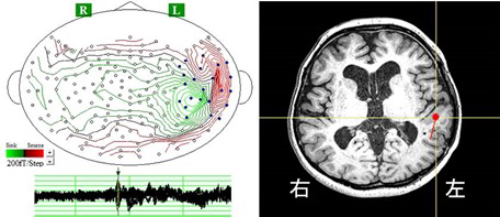

脳磁図、FDG-PET、ビデオ・ポリソムノグラフィなどによるてんかんの症候診断、原因診断、焦点診断を研究しています。

図. 脳磁図(左)による焦点診断。右はMRIにおける病巣。